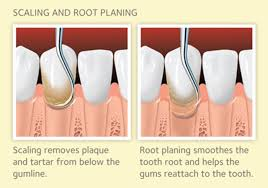

Scaling and Root Planing

Scaling and root planing is one of the most effective treatments for managing and reversing early to moderate stages of gum disease. This non-surgical procedure targets harmful bacteria beneath the gumline, removing plaque, tartar, and toxins from the surfaces and roots of your teeth to restore gum health and prevent further damage.

This treatment is typically recommended for patients with periodontal (gum) disease. When left untreated, gum disease can progress—causing gum tissue deterioration, bone loss, and eventually, tooth loss. Scaling and root planing helps stop this progression by removing the bacterial buildup responsible for inflammation and infection.